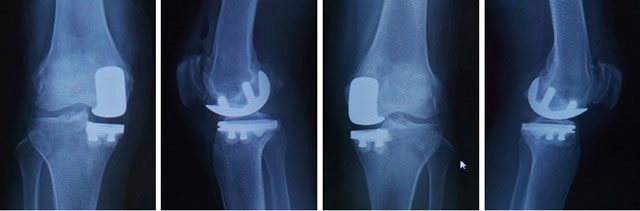

人工膝関節部分置換の一例

高位脛骨骨切り術を行う人同様に、軟骨の一部分、例えば内側だけがすり減っている場合は、その部分だけを人工関節に置き換える部分関節置換術を行う場合があります。部分置換術は骨切り術を行う人よりも高齢の人が対象となりますが、関節の痛んでいない部分や靭帯も温存できるので回復も早く、膝の曲がりも良くスムーズに動けるようになります。

手術後のレントゲン写真(両側人工膝関節部分置換術)